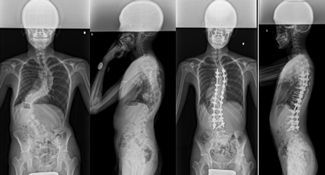

骨切りを併用した後方矯正固定術

せぼねの変形が大きかったり、再手術の場合には癒合してせぼねの骨切りを行い、再度矯正固定を行う場合があります。

5時間前後の長時間の手術となります。入院期間は小児患者様で2週間程度、大人の患者様では3週間程度で場合によってはリハビリテーション病院へ転院をしていただき、さらにリハビリテーションを行います。

腰椎固定術後後弯に対する椎体骨切り術を併用した後方矯正固定術